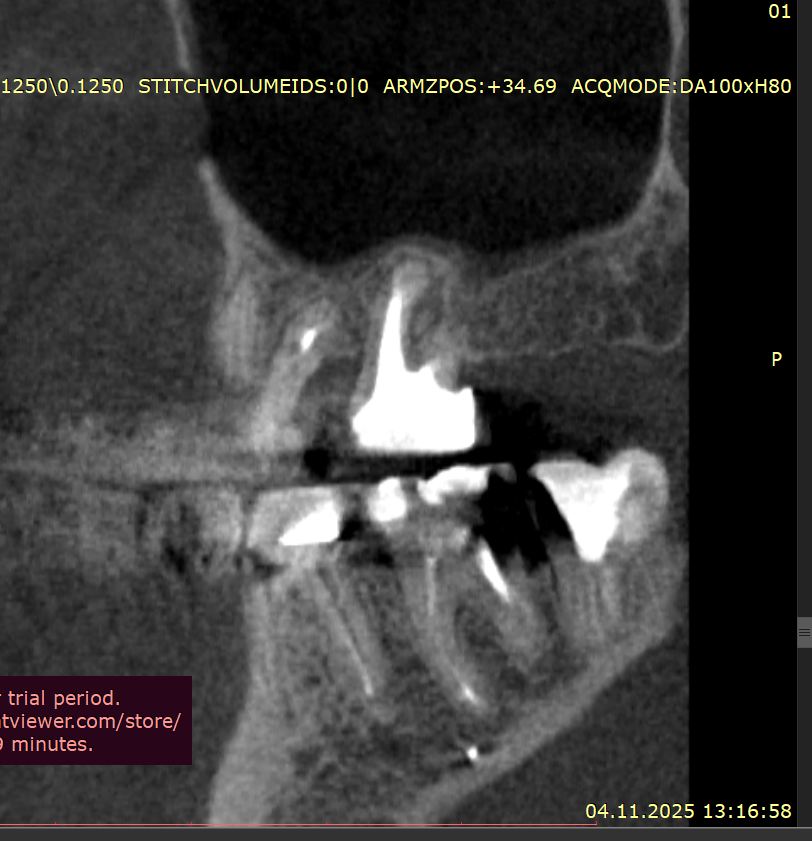

Добрый вечер Подскажите пожалуйста, вчера ел арахис, это очень редко бывает и мне такое противопоказано, и слышу один твёрдый попался немного, в момент когда накусил немного в области 4–5 зуба вверху справа, почувствовал боль, которая по сейчас сохраняется, боль чувствую именно в периодонте (к сожалению кто меня помнит с моей историей длительной я уже знаю как отличать боль по чувствительности, ту или иную), делал КЛКТ 3 недели, просто планово по поводу других зубов, посмотреть что и далее сохраняется положительная динамика после больших перенесённых периодонтитов, в вот посмотрел заодно на вот эти (открыл дайком) где вчера накусил, там нет и не было деструкции кости, зубы давно мертвые и нужно менять реставрации, зубы эти при надавливании пальцем не болят, жевать тоже не усиливается, просто ноющая периодонтальная боль извините за сленг, острой боли прям в момент накусывания арахиса тоже не было

Так же посоветуйте пожалуйста, как лучше поступить в случае 24-26, почти 2 года назад был большой периодонтит, киста пазухи. карман между 26\27, предварительно это удалось вылечить, уже 9 месяцев ничего там не болит, все спокойно, по кт медленно но есть положительная динамика, хотя все говорили удалять и только, возможно прям долгие годы эти зубы не простоят, но я хотел снять адегизивный, коронка, которая закрывает 25 отсутствующий, она крепится бабочкой между 26 и 24, и по хорошему коронки на 24,25,26 мост сделать, некоторые говорят имплант между 25, а 24 и 26 сделать просто реставрацию, я уже запутался, как лучше будет поступить ? Имплантат пока не хотел лишь по причине перенесенного в почти полтора года лонг ковида, это ужасный диагноз, в том виде в котором был у меня по крайней мере, и я хотел бы пока избежать более инвазивных процедур, хотя бы ближайшие пару лет, далее видно будет, но функционально и эстетически нужно наводить порядок, чем я и начал заниматься

Я так понимаю варианта с учетом накусывания перед этим твердого - два, трещина или травматический периодонтит, сразу лучше идти с этим зубом на микроскоп ? К тем спецам что делали 26 и 27 каналы и положительно

Рентген сегодня сделал, трещины нет, но я слышал не на рентгене не на клкт часто трещины не видны, и лишь только под микроскопом